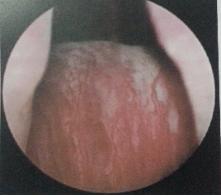

经尿道膀胱肿瘤等离子电切术:以病人的尿道为操作通路,置入等离子电切镜,将肿瘤切除后冲出,术后当天可正常下床活动、恢复饮食,避免了切口肿瘤种植的风险。在免去患者一刀之苦的同时,降低了肿瘤复发几率,极大的造福了膀胱肿瘤的患者。